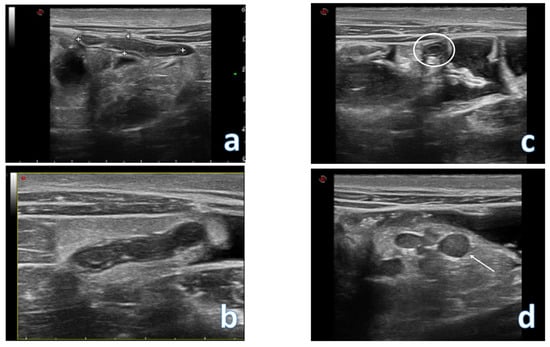

4. Acute Appendicitis

3. Flares and Complication of Inflammatory Bowel Diseases (IBD)